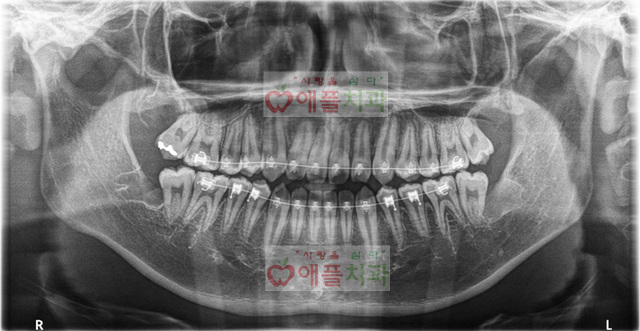

<사랑니 발치후>

내원 당일날 좌측 상, 하 사랑니 발치 하였습니다.

1주일뒤 실밥 제거하면서 반대측 상, 하 사랑니 발치 하였습니다.